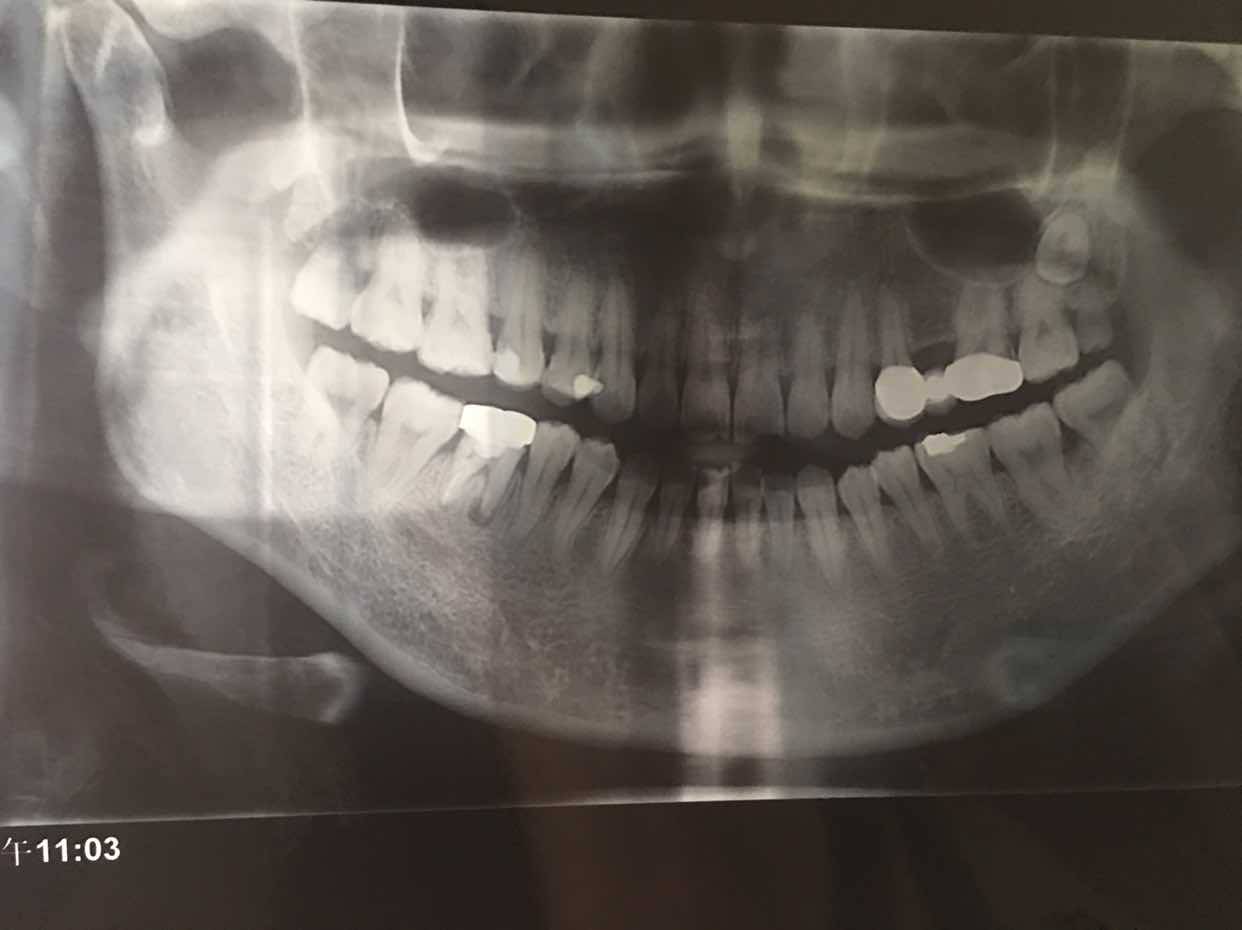

昨天终于去拔掉了右下46牙。拔之前跟大夫说明了身体状况,大夫坚持让查了个血常规才给拔。万幸的是虽然牙冠只剩了一点,但也一次性拔出来了,省去了抠牙根的麻烦。拔完后一直牙疼头晕,吃了甲硝锉和头孢,今天感觉好多了。

从三月份左上牙疼去拍片,结果发现右下46牙有炎症,本地医院一直治疗但根管一直疏通不了,建议去上级治疗,因为那边仪器先进些,可以显微根管治疗,没想到治了两次后,那边大夫也建议拔掉,没有保留的意义了。右上坏牙在上级医院做了根管治疗后,一直咬东西还有感觉,所以一直不能镶牙套,这个好悲催,本来根管治疗处理神经后大部分应该没有感觉了呀!来回折腾人力物力,这还仅仅是治疗,2500多的费用还没治彻底。牙齿有问题实在伤不起!